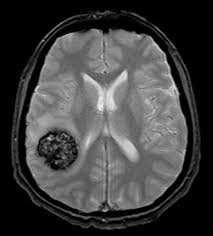

CAVERNOMAS

Un Es una malformación vascular en el cerebro compuesta por un conjunto anormal de vasos sanguíneos dilatados, que forman pequeñas cavidades llenas de sangre. Estas cavidades, llamadas “cavernas,” están rodeadas por paredes finas que son propensas a sangrar.